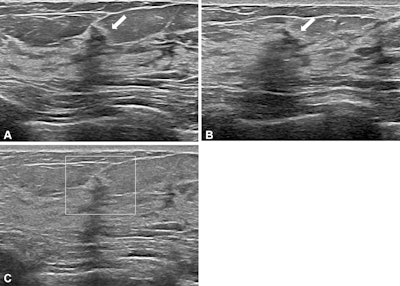

Images depict a 50-year-old woman with a lesion detected during screening ultrasound. (A) Transverse and (B) longitudinal images reveal a 0.5-cm hypoechoic lesion (arrow) in the left breast. (C) Transverse color Doppler ultrasound image does not show an increase in vascularity. Two readers classified the lesion as a mass, whereas two others categorized it as a nonmass lesion, leading to its designation as a controversial nonmass lesion. Ultrasound-guided core needle biopsy and subsequent pathologic examination confirmed a nonproliferative breast change.RSNA